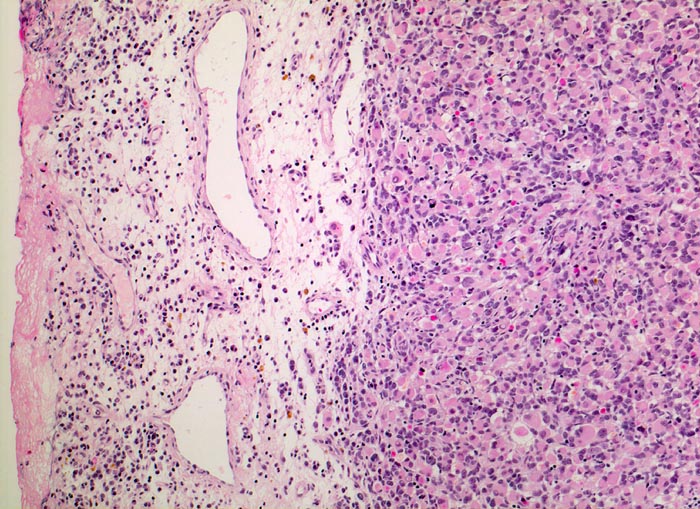

• Konjunktivalschleimhautfragment. Fibrinauflagerungen anstelle der langstreckig abgeschilferten konjunktivalen Zylinderepithelbedeckung (unten).

• Chronisches lymphoplasmazelluläres Entzündungsinfiltrat im subepithelialen Stroma mit unscharfer Begrenzung zu einem zellreichen soliden Tumor.

• Dieser besteht aus mesenchymalen Zellen mit unterschiedlicher Ausdifferenzierung.

• Die am wenigsten ausdifferenzierten Zellen zeigen wenig amphophiles Zytoplasma und ovale Kerne.

• Dominierend sind in diesem Tumor teils mehrkernige Rhabdomyoblasten mit reichlich eosinophilem Zytoplasma und exzentrischem Zellkern. Die Querstreifung des Zytoplasmas ist in der HE Färbung nur andeutungsweise erkennbar.

• "Spinnwebenzellen" mit peripheren Zytoplasmavakuolen.